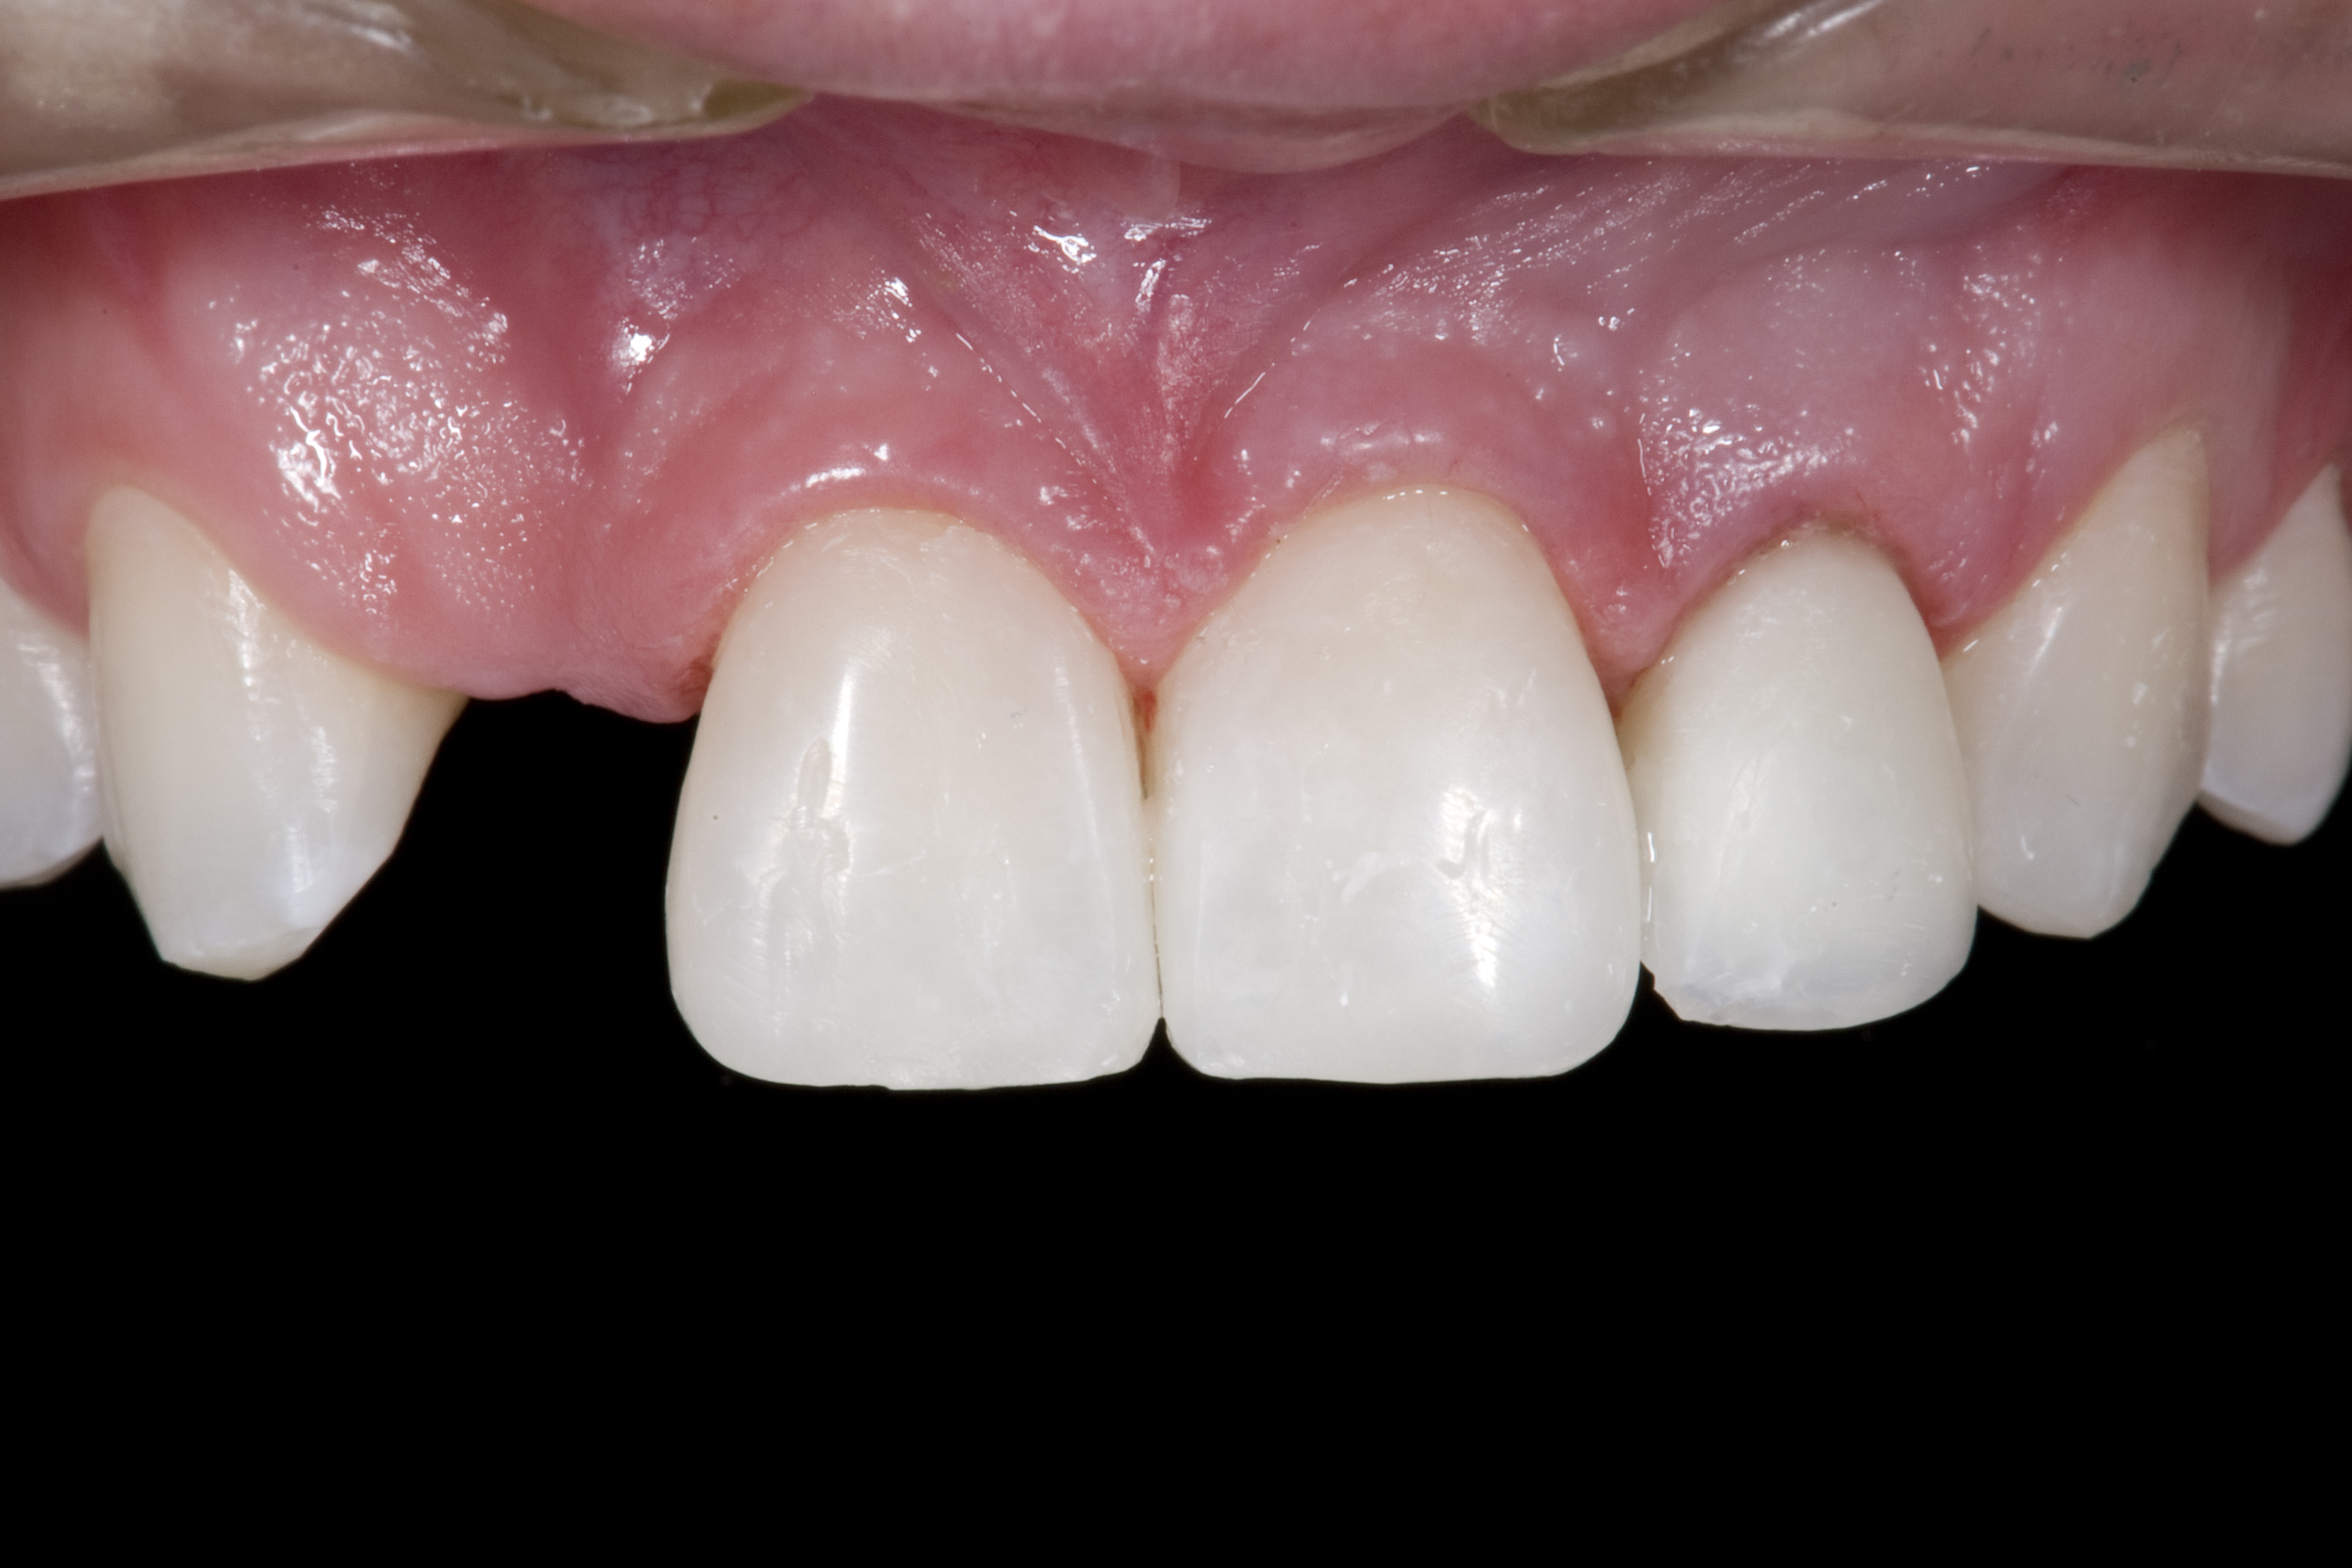

(3.) After resin-based composite bonding of the three incisors.

Figure 3

A 14-year-old patient presented to the office with his mother (Figure 1). His chief complaint involved the large spaces between the teeth created by his missing right maxillary lateral incisor and his small left maxillary lateral incisor. He desired to replace the missing tooth with an implant and create a beautiful smile. Upon examination, he was found to have a class I canine and molar relationship, but because he had a tooth size/arch size discrepancy and space distal to the right central incisor, the remaining incisors had drifted to the right. The left maxillary lateral incisor was peg-shaped and in a cross bite position. Studies have shown a clear association between congenitally missing teeth and reduced tooth size.59-62 Because he was only 14 years old at the time and could not have implants placed until the cessation of growth (somewhere in the vicinity of 22 years old), he was sent to the orthodontist for alignment of the teeth.16,17 After 2 years of orthodontics, the appliances were removed, and his tooth coloration was improved using carbamide peroxide bleaching (Figure 2). Because some form of provisional needed to be placed until he was finished growing, a double-wing metal resin-bonded bridge was chosen. As discussed earlier, this is the ideal transitional prosthesis for patients that have congenitally missing maxillary lateral incisors. The benefits of this type of prosthesis include its ability to be removed and rebonded during the surgical phase of treatment and its ability to retain the roots in their proper position after orthodontic treatment.16 The final plan for the patient was to increase the width of the central and the maxillary left lateral incisor, utilizing porcelain laminate veneers to achieve the appropriate width/length ratio of 80%. A wax-up was created to idealize tooth size, a putty matrix was made from the wax-up to facilitate bonding of the incisors, and a non-precious, double-wing metal resin-bonded bridge was fabricated for lateral incisor replacement. Once the teeth were bonded to ideal size, the “Maryland Bridge” was fabricated from a polyvinyl arch impression with the newly bonded teeth (Figure 3). The metal frame was cast from a non-precious alloy to allow for fabrication of a very thin frame and to create a better surface for bonding. After sandblasting the internal aspect of the frame with CoJet™ silica (3M ESPE), accomplishing salinization, and executing cementation with a dual-cure resin cement, a fairly good adhesion to the frame was anticipated.29 The enamel surface was etched with phosphoric acid for 30 seconds, the primer (Single Bond Plus, 3M ESPE) was applied to both the internal surface of the sandblasted framework and the etched enamel, and the bridge was cemented with RelyX™ ARC (3M Espe) dual-cured resin cement (Figure 4 and Figure 5).